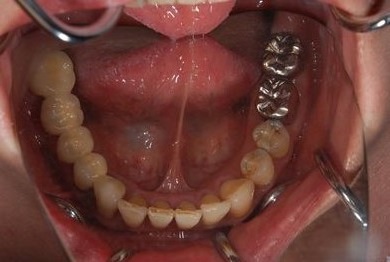

インプラントの症例写真 IMPLANT

抜歯即日スピードインプラント治療

| 性別/年齢 | 女性 / 44歳 | ||||||||||||||||||||||||||||||||

| 主訴 | 上のさし歯がグラグラする。インプラントにした方が良いのか、相談したい。 | ||||||||||||||||||||||||||||||||

| 治療方針 | 抜歯と同時にインプラントを埋入し、治療期間を短縮する。 | ||||||||||||||||||||||||||||||||

| 治療内容 | インプラント2本(抜歯即日スピードインプラント)、メタルボンドセラミック2本 | ||||||||||||||||||||||||||||||||

| 総治療費 | 458,588円 | ||||||||||||||||||||||||||||||||

| 治療期間 | 6ヶ月 |